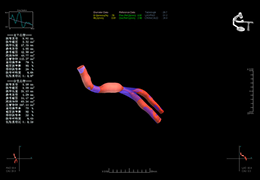

View X-Ray CT & MRI Scans Fast and Easily

Designed for surgeons, Pro Surgical 3D makes it easy to view patient scans quickly. Pro Surgical 3D facilitates the optimal 3D treatment and assessment workflows based on X-ray CT and MRI scans – and best of all, it’s FREE!

High-quality and fast 3D reconstruction and 3D rendering

Performs 3D reconstruction and volume rendering.

Instant and interactive surface extraction and export to STL and PLY formats.